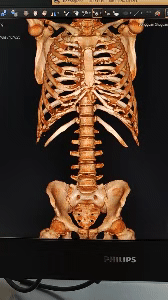

3D重建,立体呈现

飞利浦Incisive AI CT还具备3D重建成像技术,能够将复杂的解剖结构以三维的形式呈现出来,为医生提供更为直观的视觉辅助,从而帮助医生更好地理解和解释病变情况,提升诊断准确性。